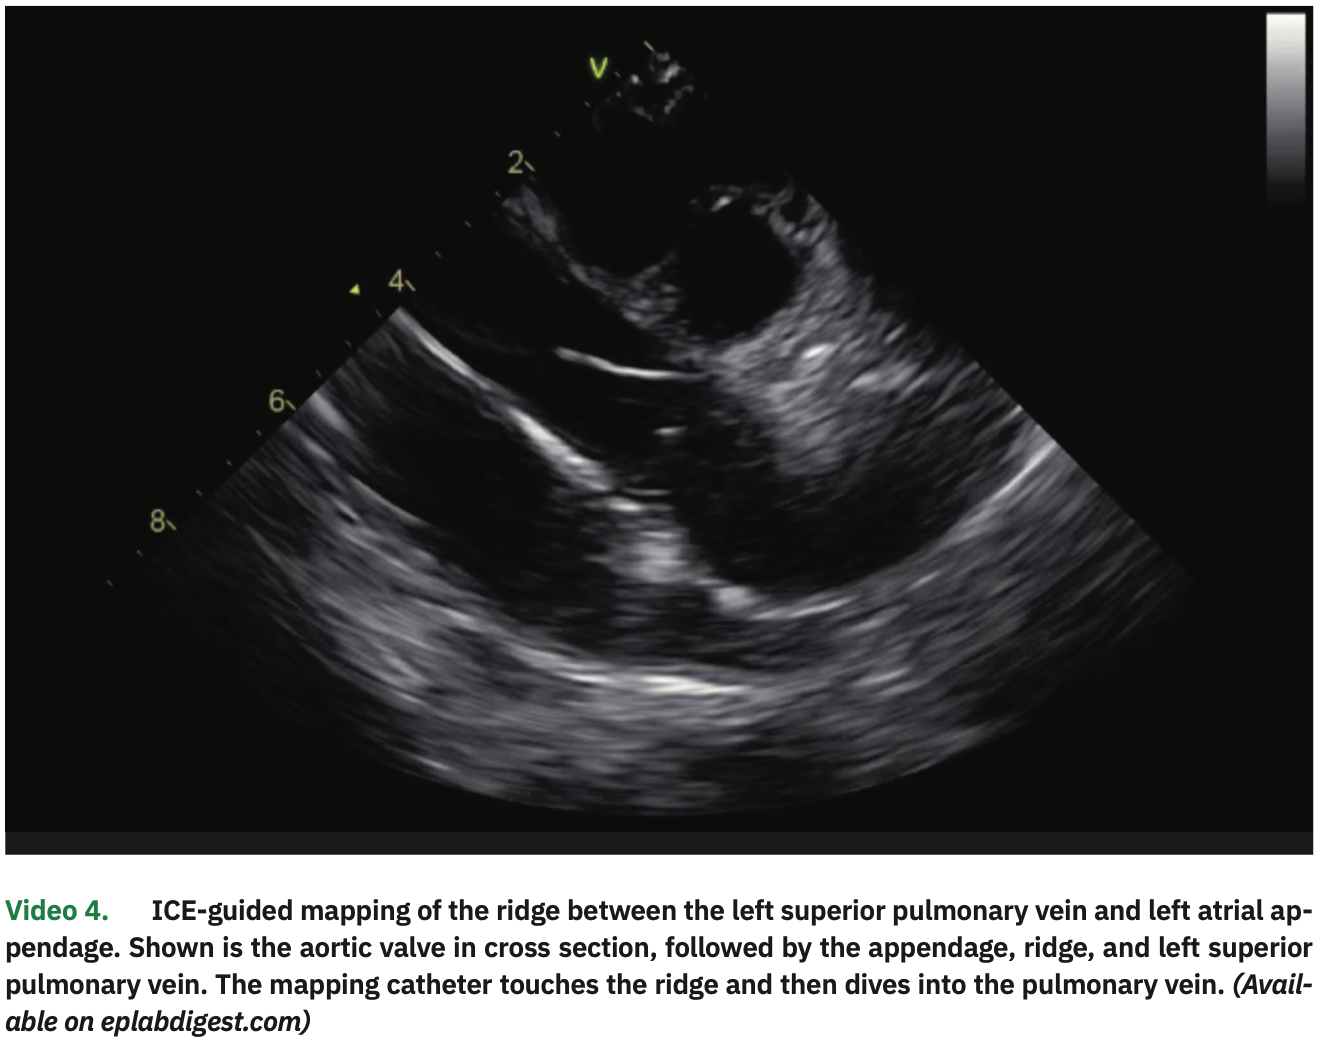

The LA and PV anatomies were reconstructed with a high-density map using the multipolar catheter. In particular, the ridge between the LSPV and left atrial appendage was visualized on ICE (with the catheter placed in the right ventricle; Video 4) and its position was manually annotated in the EA map. After calibrating the contact sensor, point-by-point circumferential PV isolation was performed for both pairs of veins, using 35W of power and contact force between 10-20 g, until electrogram elimination. Esophageal temperature rise occurred in the posterior segments of the left PVs, where shorter (5- to 10- second) applications with lower power (25-30 W) were performed. Adenosine infusions (18 mg) confirmed PV isolation without dormant conduction.